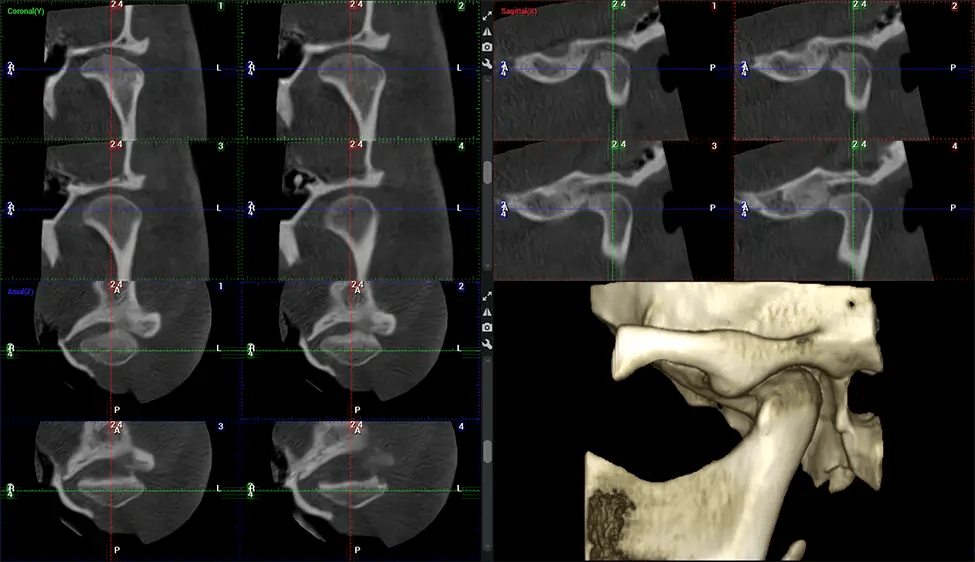

After the scanning process, the captured X-ray images are processed by the CBCT software, which applies algorithms to reconstruct a detailed 3D image of the scanned area. The software compiles these individual X-ray images and creates a digital 3D representation of the patient’s anatomy. The reconstructed 3D CBCT image can be viewed and analyzed by the dentist or radiologist. This image can be manipulated, rotated, and zoomed in or out to examine specific structures and evaluate the patient’s condition.

Planmeca Viso G7 CBCT ( Cone Beam CT Scan ) is designed to surpass the demands of industry leaders, specialists, and large institutions. It’s has a large ø25×30 cm sensor with four built-in cameras. It can capture unlimited volume sizes from a ø3×3 cm to a ø30x30cm volume capturing the skullcap through C7 on the cervical spine. The Planmeca Viso G7 offers the industry’s largest single volume scan of ø30×19 cm. It’s poised to handle advanced imaging modalities such as Planmeca ProFace® and Planmeca 4D™ Jaw Motion technology. The occipital head support allows an unimpeded view of facial tissue.